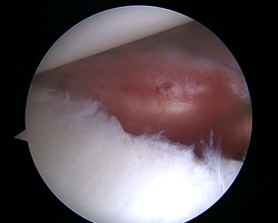

The patient is a 50 year-old female with Adhesive Capsulitis. Although her initial pain dissipated, she continued to suffer from a significant decrease in range of motion. After two years of symptoms, she decided to undergo an arthroscopic 360 degree capsular release. A combination of arthroscopic biters and shavers are used to release the capsule, but avoid injuring the underlying rotator cuff muscle and neurovascular structures (photo 1). The capsule should only be 1-2 mm in width, but with adhesive capsulitis the capsule can be up to 10 mm thick. At the time of surgery, her anterior and posterior capsule appeared thickened and stiff (photos 2,4). After surgery, the anterior and posterior capsule has been released (photos 3,5) and a normal range of motion has been restored. She went on to have full range of motion, was able to perform all of her activities of daily living, and returned to yoga and all of her sport activities.